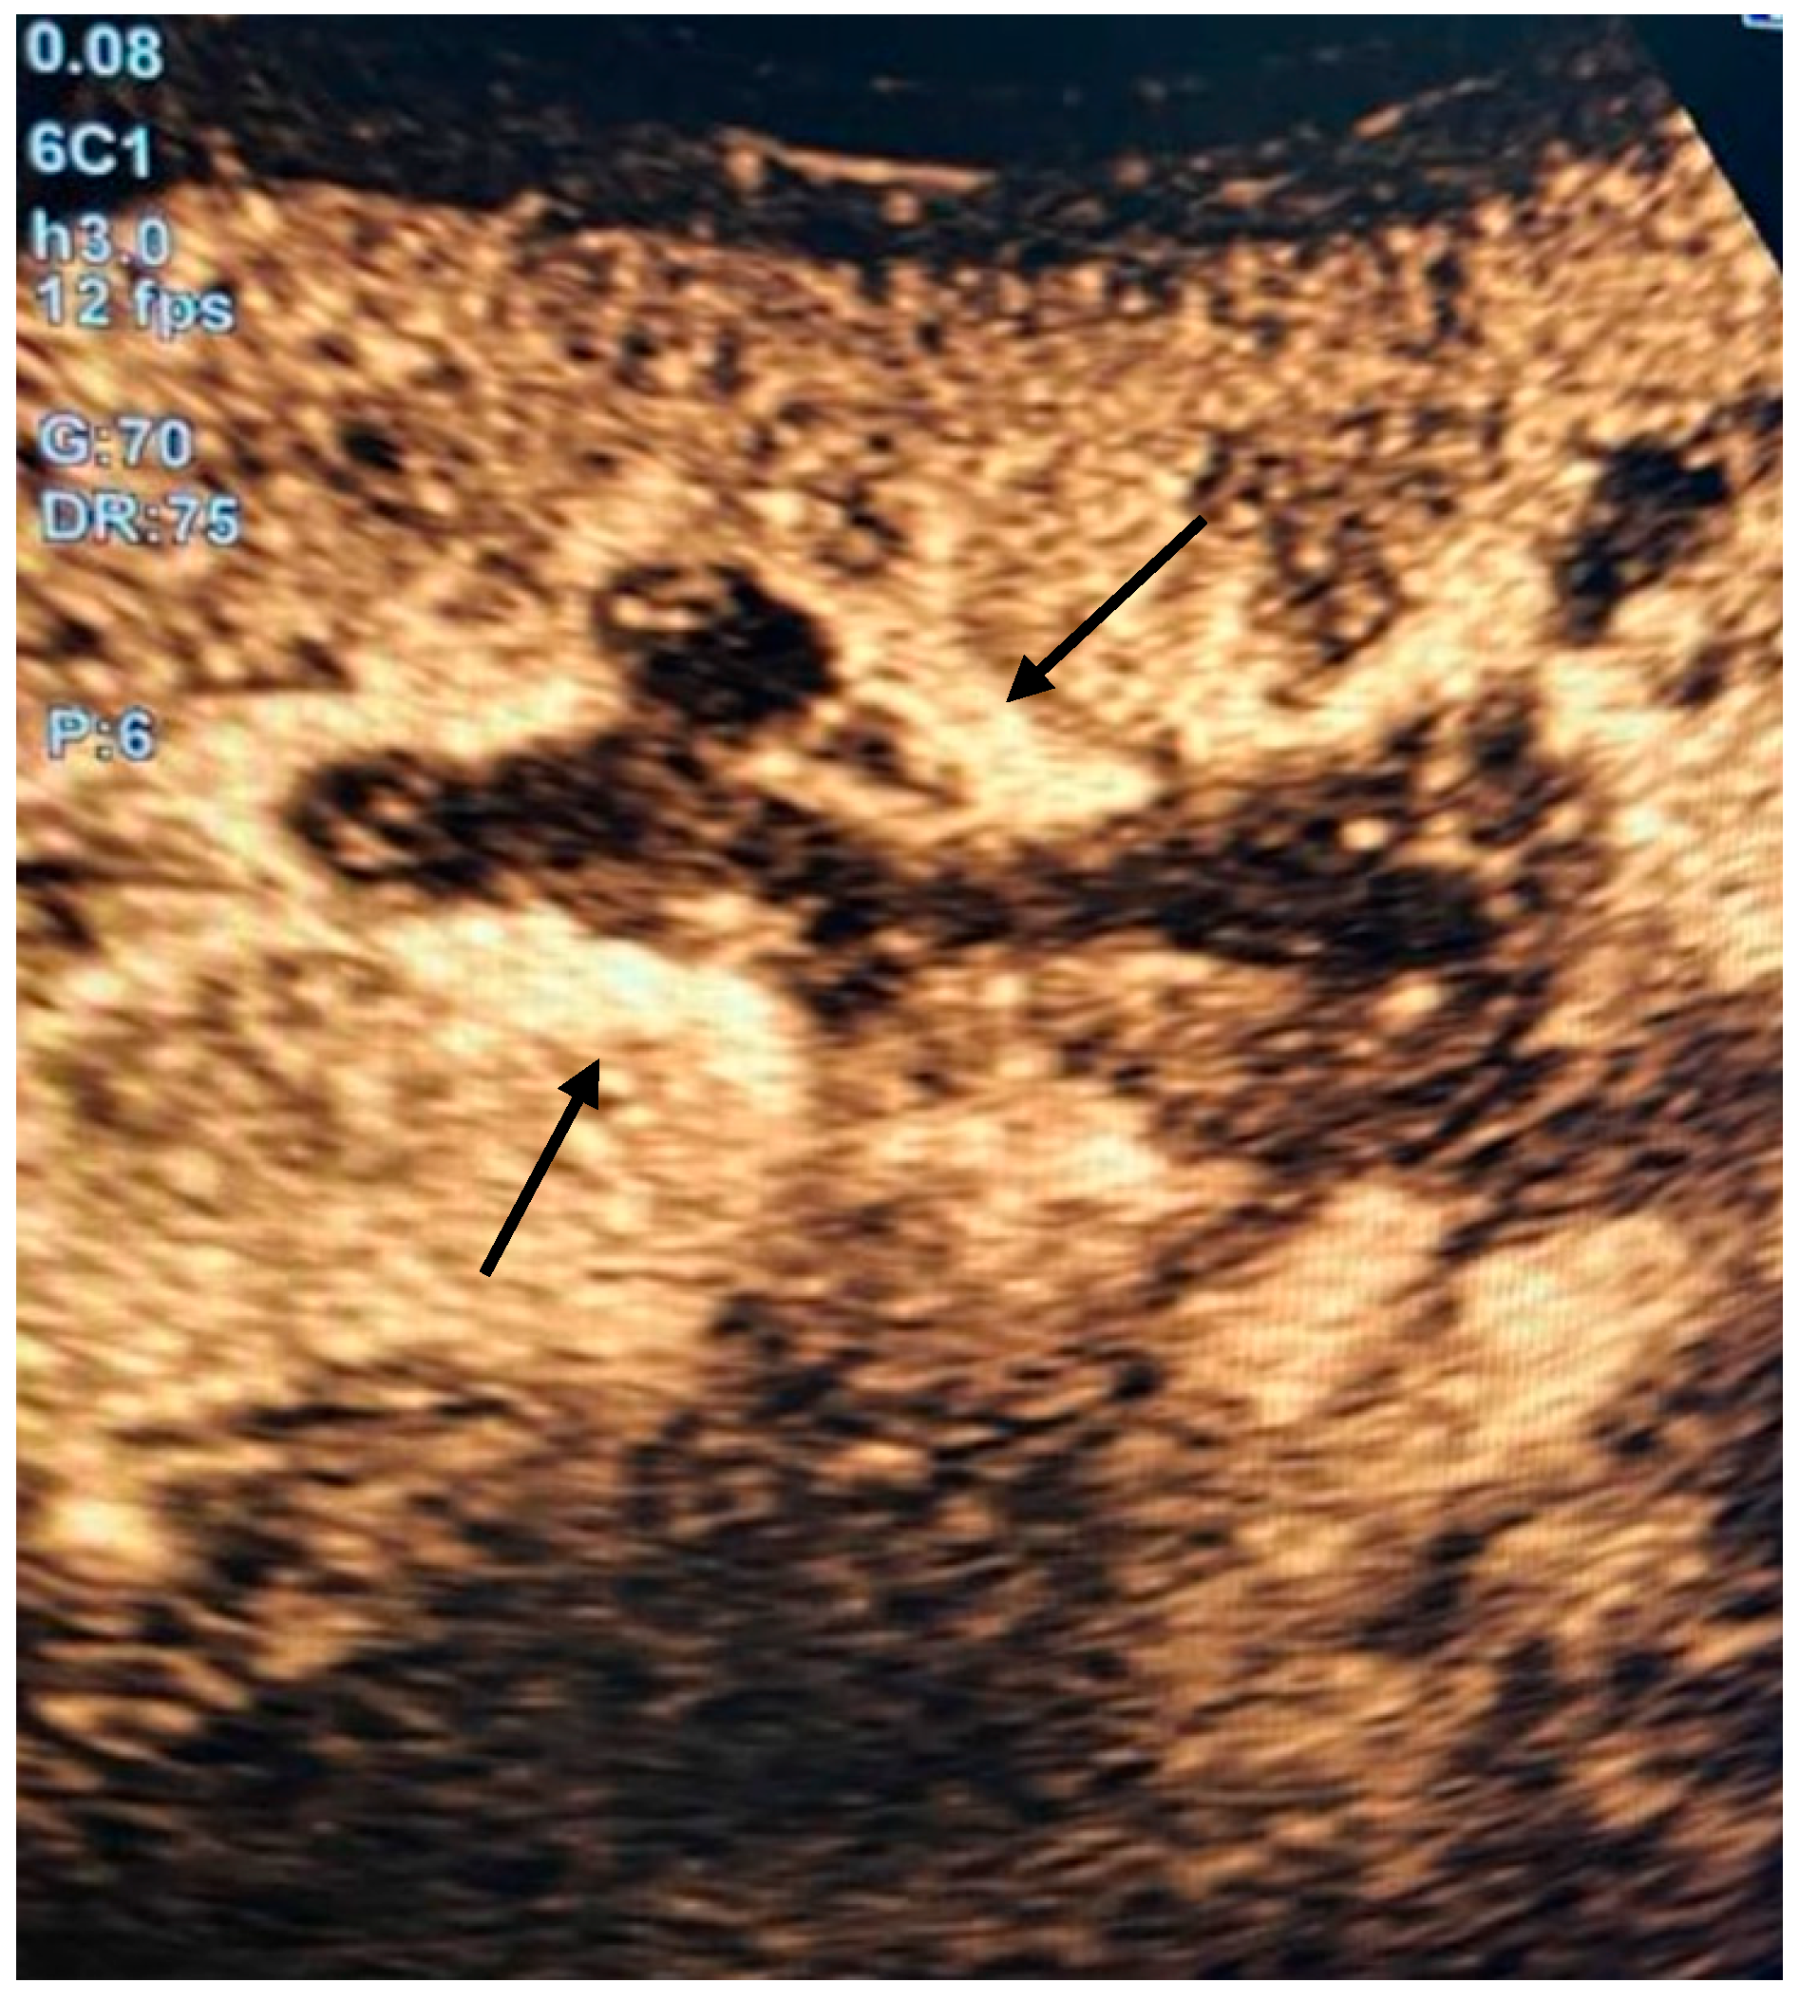

2. Detailed Case Description